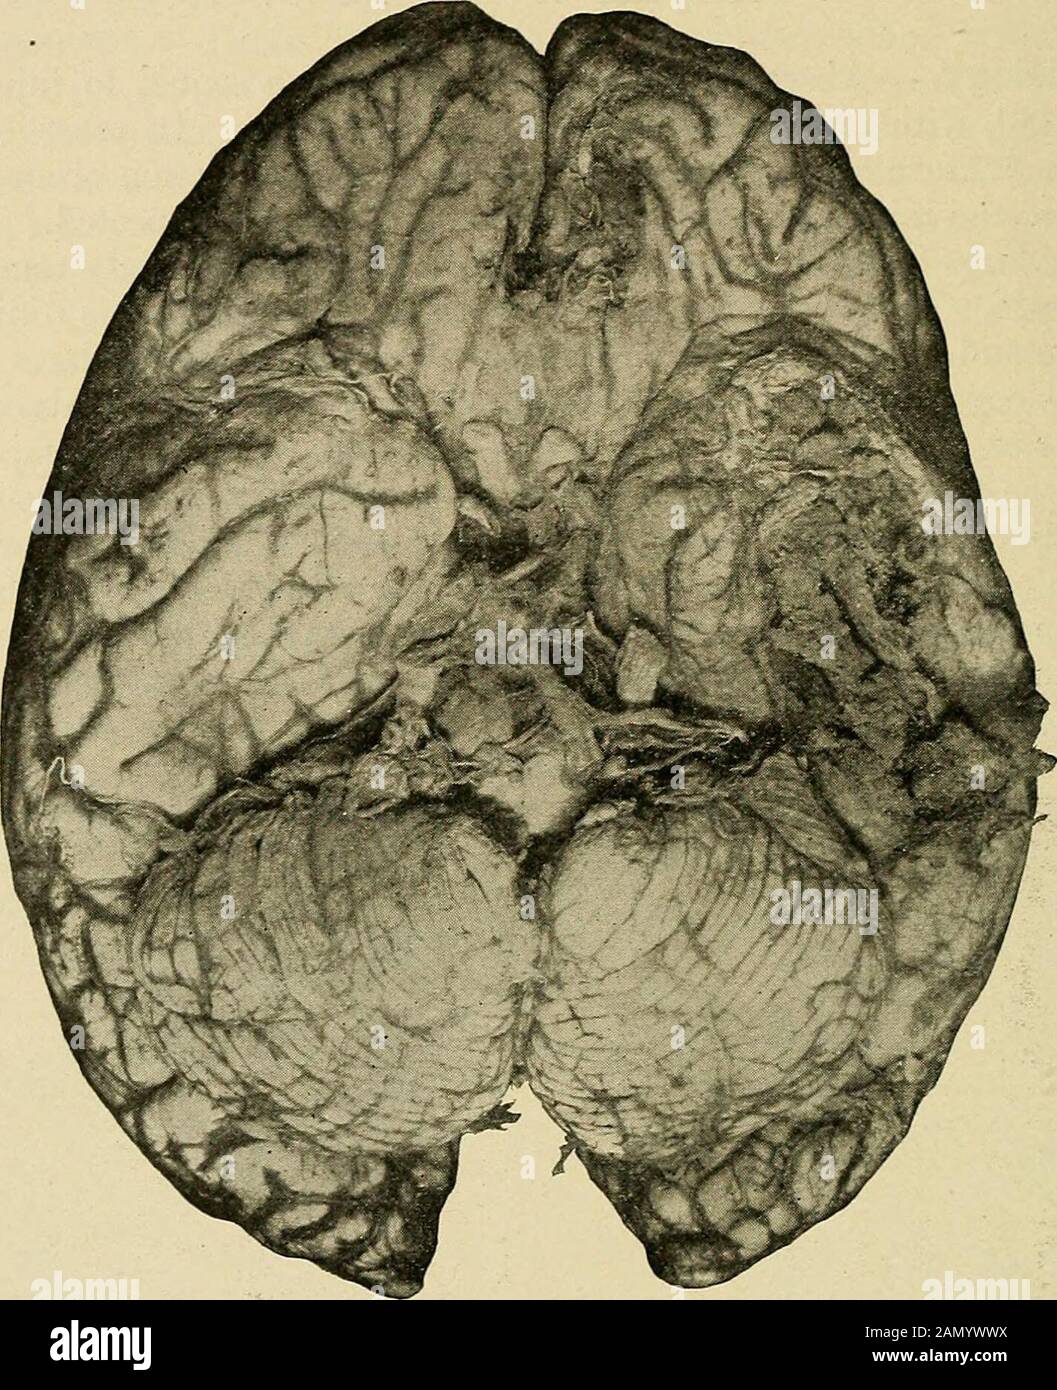

Malattie Nervose Organiche E Funzionali Un Testo Libro Di Neurologia Grande Ascesso Nella Regione Parietale Inferiore Secondario Alla Frattura Della Puu Si Puo Vedere La Capsula Spessa Dell Ascesso Nel Caso Di Un Neonato